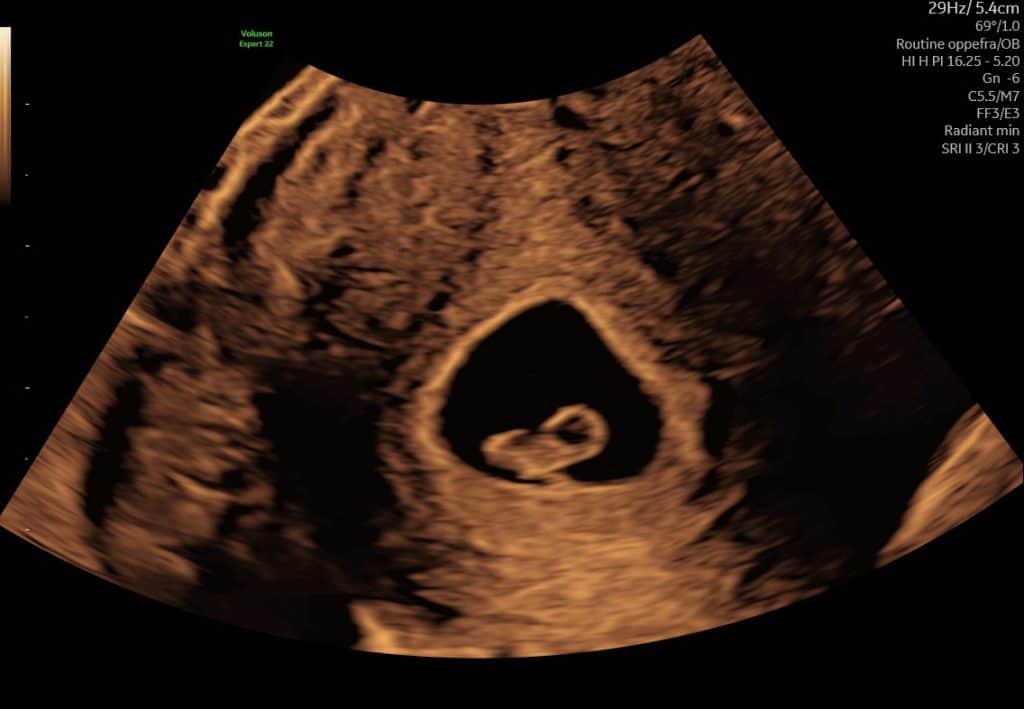

Tidlig scanning uge 6 foster i livmoderen

Tidlig scanning uge 5-6, blommesæk i livmoderen

Eksempel på ultralyd i uge 5–6. Det er normalt, at ikke alle strukturer kan ses på dette tidspunkt.

Nogle gange giver korte ultralydssekvenser et bedre indtryk end stillbilleder alene.

Kort ultralydssekvens fra uge 6 hvor der kan ses blommesæk og tidligt fosteranlæg.